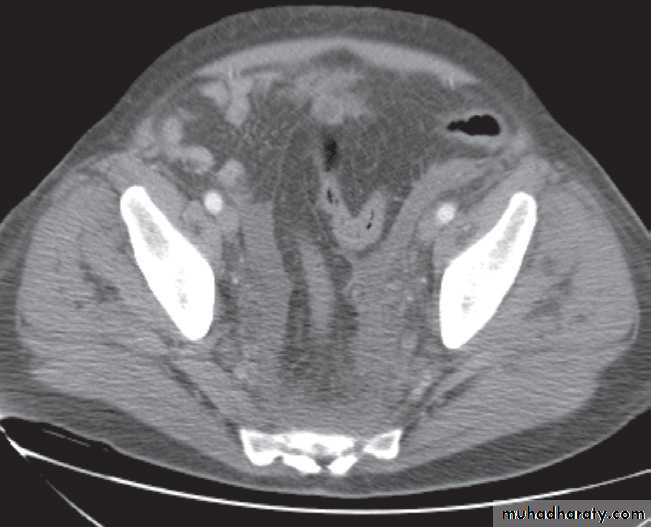

-Tumours. Carcinoma of the cervix, ovary and rectosigmoidcolon and malignant lymph node enlargement are frequent

causes of ureteric obstruction. CT is the ideal method of diagnosis because it shows the tumour mass as well as the level of obstruction.

-Retroperitoneal fibrosis. In most cases, no cause can be found for this benign fibrotic condition, which encases the ureters and causes obstruction. When first seen, only one side may be obstructed but, eventually, the condition becomes bilateral.

The obstruction is usually at the L4/5 level. Fibrosis may extend superiorly to surround the kidneys and inferiorly to involve the pelvic side walls. CT has become the diagnostic method of choice.